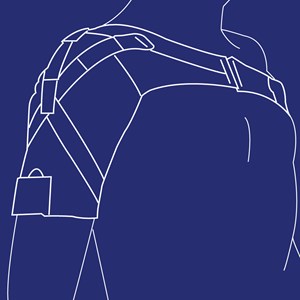

Scapula Alata ortose

Type: pdf

Størrelse: 1161 KB

Skulderortose (SdO)

Type: pdf

Størrelse: 1794 KB